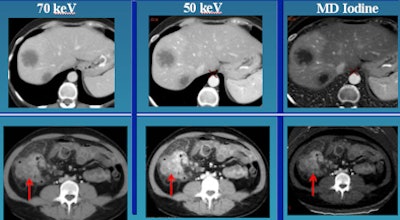

![]() |

| Top row: In liver perfusion abnormality, differential enhancement is better seen on material differentiation (MD) iodine image. Bottom row: In CT enterography, MD iodine and lower keV material composition (MC) images accentuate bowel wall enhancement. |

In the imaging of renal cell carcinoma at 120 kV versus 50 kV, lesion enhancement is maximized at the lower kV setting, he said. In a patient with liver metastases, moving from 70 kV to 50 kV improves tumor definition and also better defines the area around the tumor.

"This can translate into a better tumor target for purposes of treatment planning," Sahani said. "For example, in proton therapy for liver tumors they need to have a better definition of the tumor target, and one can exploit this for therapy planning."